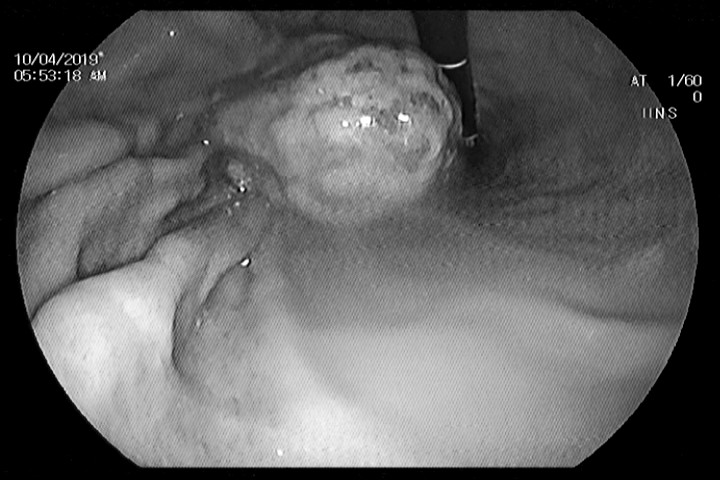

Hình ảnh nội soi khối bã trong dạ dày bệnh nhân. (Ảnh: BVCC)

Điều bất ngờ là trong quá trình nội soi, bác sĩ đã phát hiện một khối bã thức ăn màu vàng kích thước 3x4cm cứng chắc trong dạ dày người bệnh. Bên cạnh đó, ở vị trí bờ cong nhỏ còn có một ổ loét kích thước khoảng 1cm; niêm mạc dạ dày vùng hang vị bị phù nề, nhiều chấm xung huyết. Người bệnh được chỉ định điều trị và theo dõi tại nhà trong 2 tuần. Sau 2 tuần đến kiểm tra lại nếu khối bã thức ăn vẫn chưa được đào thải hết, các bác sĩ sẽ tiến hành gắp nốt ra khỏi dạ dày người bệnh.

Trao đổi với VTC News, bác sĩ CKI Vũ Hồng Thái, Giám đốc Phòng khám Đa khoa, Bệnh viện Đa khoa tỉnh Phú Thọ cho biết, đây không phải lần đầu tiên đơn vị điều trị thành công những trường hợp dị vật và khối bã thức ăn trong dạ dày bằng kỹ thuật nội soi. Tuy nhiên, khối bã kích thước lớn và cứng chắc như của người bệnh L. là trường hợp tương đối hiếm gặp.

Theo bác sĩ Thái, bột nghệ khi vào dạ dày quyện cùng chất xơ có trong thức ăn sẽ tạo nên một khối bã kết dính trong dạ dày người bệnh, gây đau bụng và tổn thương dạ dày. Nhờ kỹ thuật nội soi can thiệp, người bệnh sẽ tránh phải phẫu thuật, mà chỉ cần điều trị và theo dõi tại nhà, không cần nằm viện.